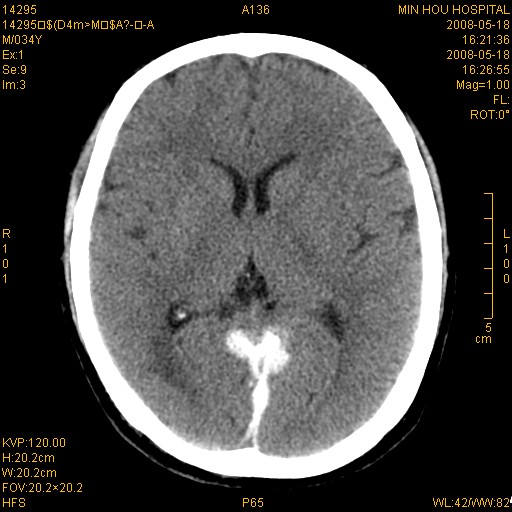

标题: CT13617:双顶叶白质水肿伴大脑镰小脑幕广泛钙化 [打印本页]

标题: CT13617:双顶叶白质水肿伴大脑镰小脑幕广泛钙化

多年前频发抽搐生活不能自理,行ct平扫,诊断为双顶叶占位。因贫未能进一步检查。

目前偶有抽搐,能从事油漆工作。原片未能获取。

双侧侧脑室后脚旁对称性低密度影,符合肾上腺白质营养不良(成人型)改变    小脑幕及大脑廉钙化  可考虑为生理性

支持:1、肾上腺白质营养不良.2、小脑幕、大脑镰广泛钙化。3、建议进一步检查。

硬脑膜钙化是主因,双侧顶叶白质密度减低是可能由于静脉路回流受阻所致。